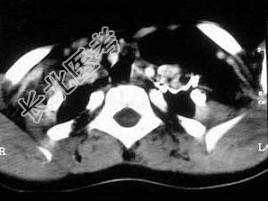

- 单项选择题女,17岁, 发现左侧颈部包块半年余,PE: 病灶质软,境界不清, 无压痛,CT如图所示, 最可能的诊断是 ( )

D、颈部淋巴管瘤